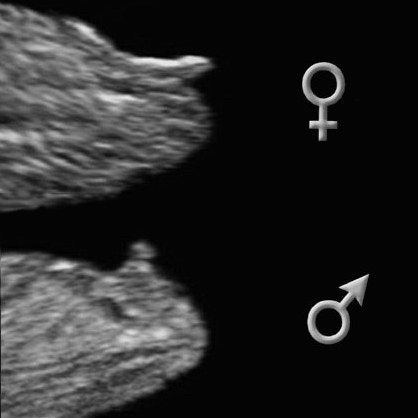

А вот фото, которые я нашла на просторах интернета с "инструкцией" на мальчика

И вот еще фото

Все фото-примеры как раз рассказывают про определение пола на 13-ой недельке